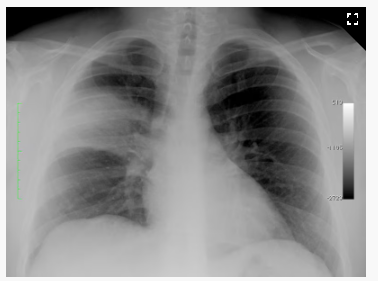

Diagnostic Procedures

Chest X-Ray

Shows lung consolidation

May be negative early in disease

Important in older adults due to vague early symptoms

Pneumonia (Image)